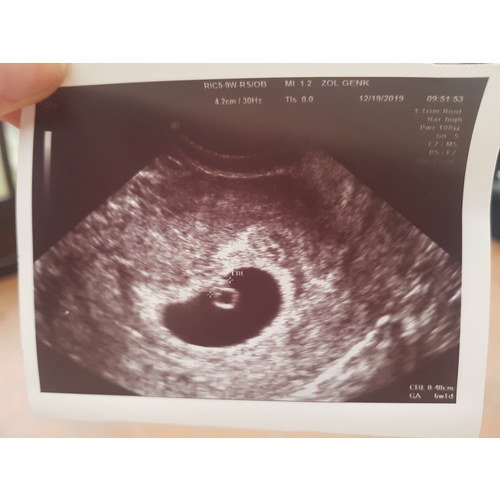

Mijn echo met 6 weken en 3 dagen. Kloppend hartje gezien.

Was wel met medische reden dat ik zo vroeg een echo heb gehad.

Nu de 27e weer een met 8 weken en 6 dagen.